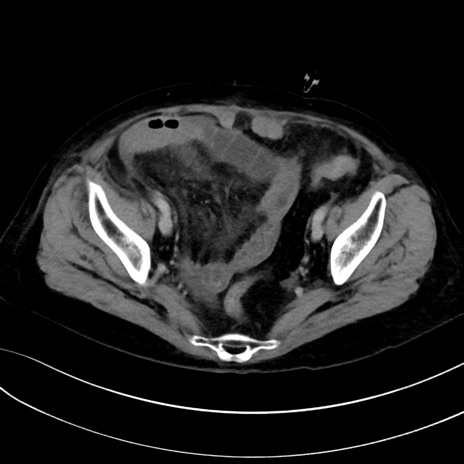

症例13 CT(横断像)1日半後